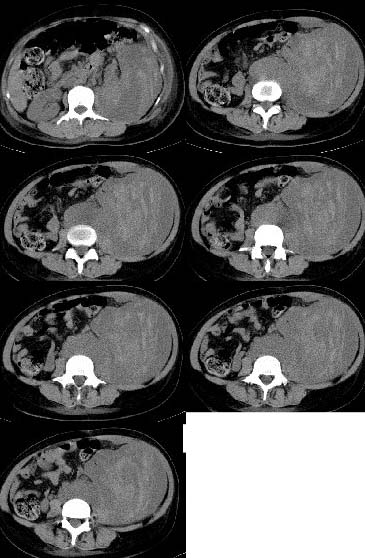

女,34岁,发觉腹部包块1周,查体:腹膨隆,左腹自肋下至髂嵴扪及10x8cm左右包块,触痛明显,固定

病变自脾下至盆腔,范围广泛,左肾显示不清,似向前内侧推移,考虑病变来源于腹膜后;病变边界不清恶性可能性大;建议增强进一步明确。

平扫病灶密度不均匀,病灶内可见条样高密度影,边清。该病例未见增强。

根据平扫密度不均匀,其内条样高密度影,考虑来源于腹膜后;

根据病史一周,有触痛,我觉得血肿不能除外,可以继续询问是否有外伤史。

到三级医院增强结果出来了,是腹主动脉瘤破裂出血,血肿形成。